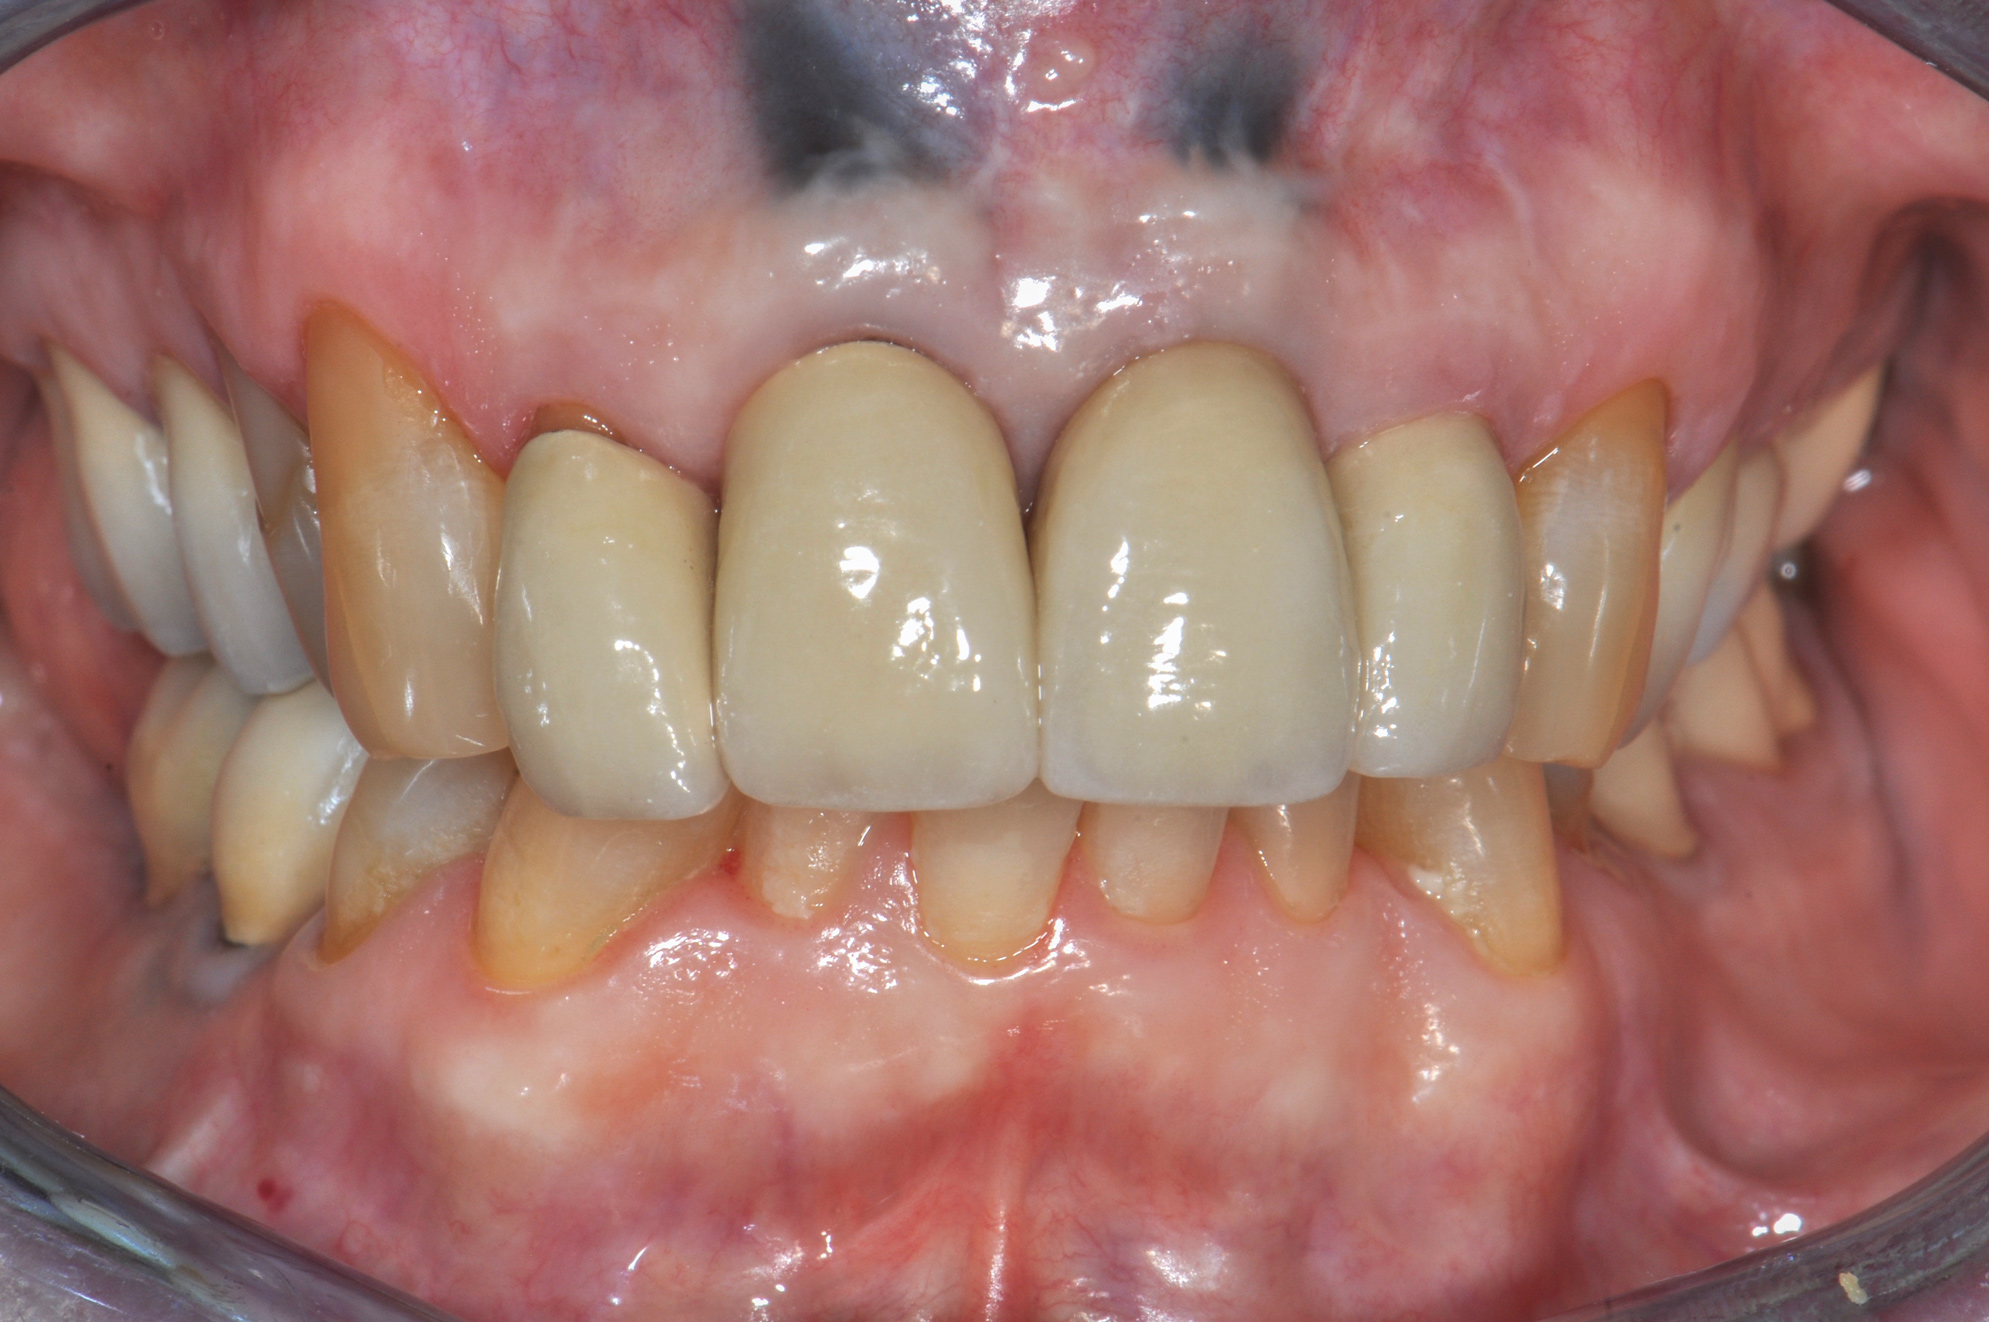

Fig 17. Facial (Fig 17) and occlusal (Fig 18) views, 3 years postoperative, of implants Nos. 7 and 10, fully guided with 3D placement of 3.3-mm x 12-mm implants with non-loading of both sites. Patient was high esthetic risk profile. Key Nos. 7 (SCTG) and 8 (immediate contour management) were not used. Facial bony concavity with loss of ridge width was noted on No. 7 along with show-through of titanium abutments (periodontist: Jeff Ganeles, DMD).

Figure 17

Finally, another example of an "unlucky" esthetic outcomeis illustrated in Figure 17 through Figure 19, which show the 3-year postoperative follow-up of the fully guided (coDiagnostix®, Dental Wings, dentalwings.com) 3D placement of No. 7 and No. 10 implants (Straumann Bone Level Narrow Connection Roxolid® SLActive, Straumann) in a 34-year-old high esthetic risk profile female patient with non-loading of both implant sites. For this patient, eight of the 10 keys were followed, with the exceptions being key Nos. 7 (SCTG) and 8 (immediate contour management). Esthetic complication was noted, especially on implant No. 7, with a facial bony concavity with loss of ridge width and show-through of the titanium custom abutments (ie, "graying" of soft tissues) due to colorimetric changes of the marginal tissues.